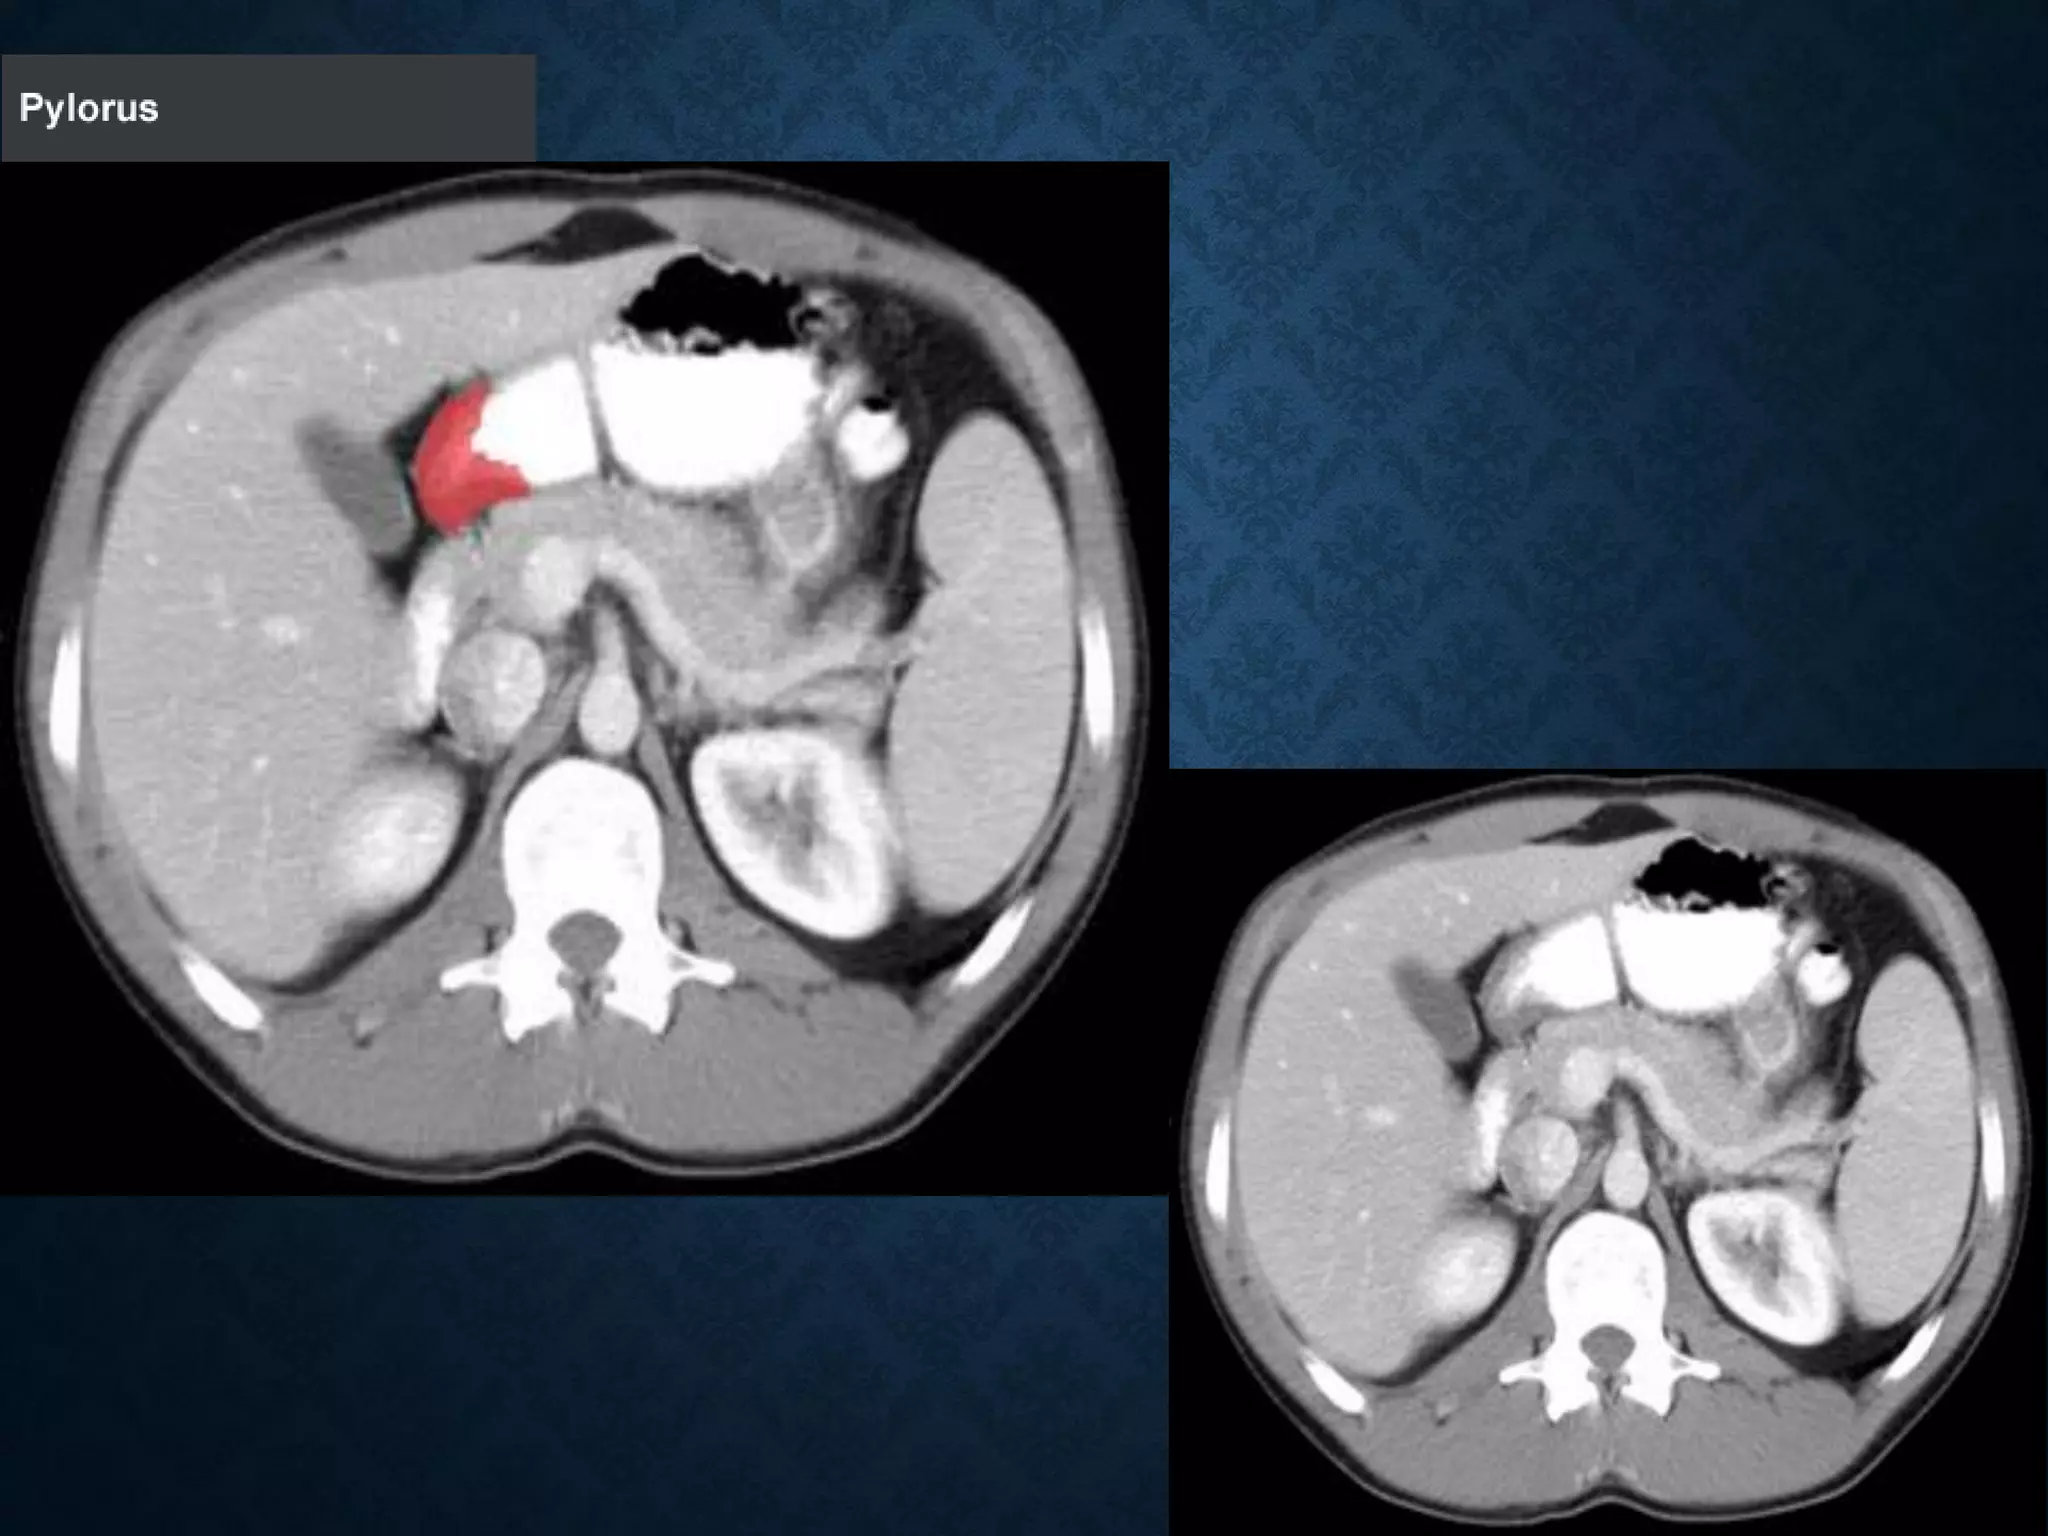

PYLORUS

STOMACH